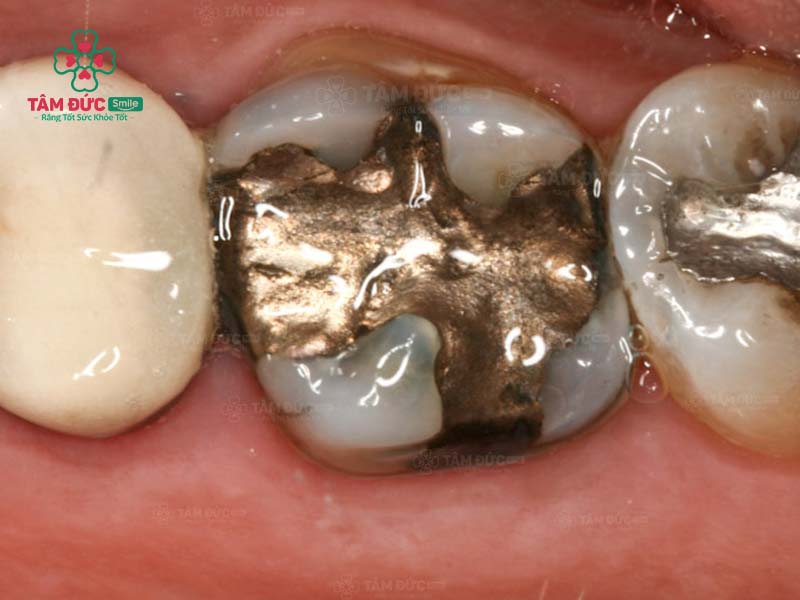

2.1. Amalgam

Amalgam (hoặc còn gọi là trám bạc) là vật liệu trám răng có màu bạc, xuất hiện từ lâu trên thị trường nha khoa. Thành phần chủ yếu của Amalgam bao gồm: Bạc, kẽm, đồng, thiếc và thủy ngân.

Loại vật liệu này rất bền, có độ chịu lực tốt và giá thành rẻ nhất trong tất cả các loại vật liệu trám răng. Tuy nhiên, do Amalgam có màu sắc khác biệt với màu răng, nên không được đánh giá cao về thẩm mỹ.